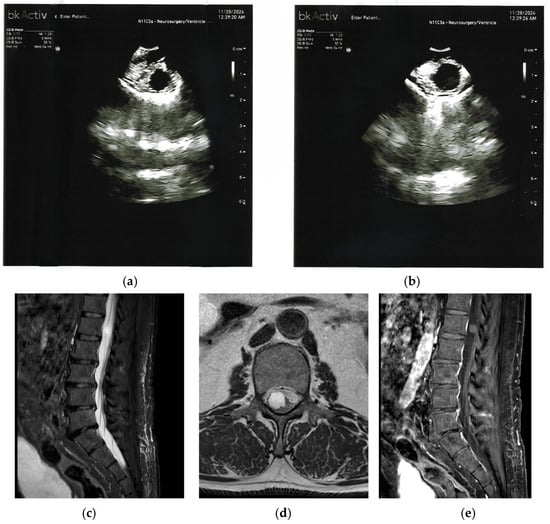

3. Spinal Chronic Subdural Hematoma (CSSDH)

| Spinal Chronic Subdural Hematoma (CSSDH) | Hyperintense on T1 or T2 (late subacute); isointense or hypointense (chronic); elongated dorsal collection with cord displacement. | Hypoechoic or anechoic subdural collection beneath echogenic dura; internal echoes or septations; bounded by echogenic membrane. |